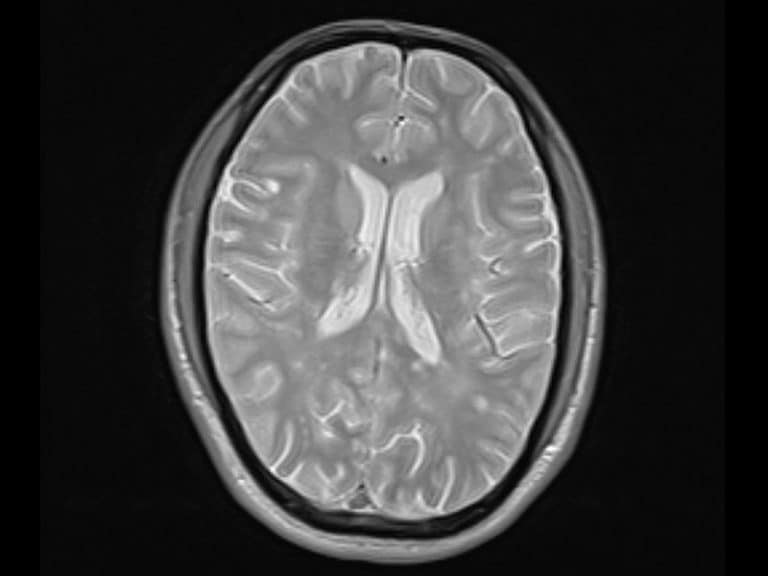

ولتحديد الآلية الدقيقة المعنية، قامت شو وفريقها بإخضاع 21 شخصاً مشاركاً لاختبار يسمى مهمة وقف الإشارة، وذلك أثناء تواجدهم في جهاز التصوير بالرنين المغناطيسي الوظيفي. وتقول شو: “إنه ينطوي على إلغاء حركة تم القيام بها بالفعل”. وفي هذه الحالة، كانت الحركة هي حركة العين، حيث تم عرض إشارة على المشاركين، إما إلى جهة اليسار أو اليمين، وكان عليهم أن يحركوا عيونهم للنظر إلى الهدف بأسرع وقت ممكن. وبعد أن بدأوا بالحركة، تم عرض إما دائرة زرقاء أو صفراء، حيث تعني إحداهما التوقف، والأخرى تعني الاستمرار، وكان عليهم إما مواصلة أو إلغاء حركة العين.

واتخذ الفريق خطوة إضافية بتتبع آثار نفس المهام على دماغ القرد. إذ يمكن للعلماء قياس استجابة الخلايا الفردية لدماغ القرد خلال إحدى المهام، بينما عند البشر، فلا يمكنهم سوى رؤية المناطق الأكبر التي تأتي من خلال التصوير بالرنين المغناطيسي. وتقول شو: “لدينا بيانات القرود وبيانات الإنسان حول المهمة، ولذلك هناك أدلة متقاربة. إذ يتم دراسة كل من تصوير الدماغ والاستجابة العصبية المباشرة.”

بالنسبة لبراون، فإن الأدلة المشتركة من صور الدماغ البشري والخلايا العصبية الفردية تدعم نتائج الدراسة. ويقول: “الأدلة تتراكم بشكل جيد جداً”.